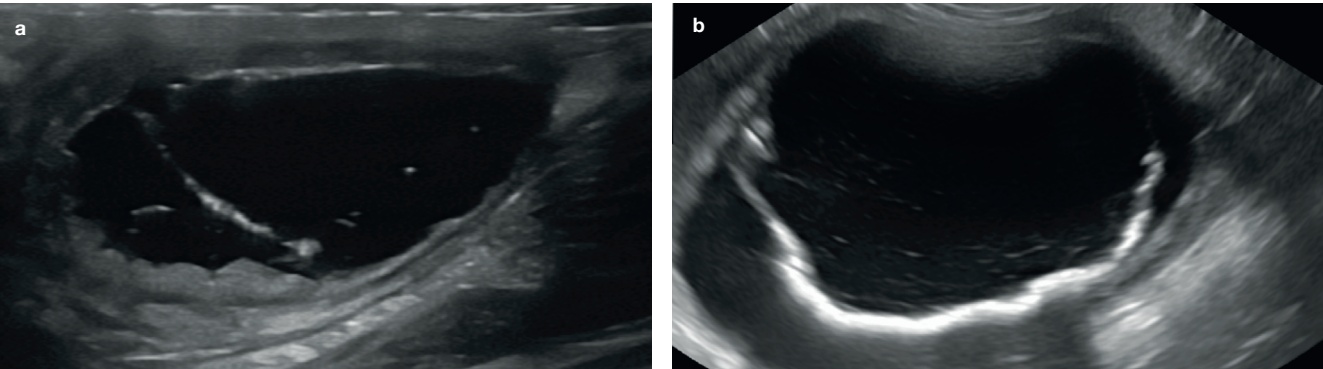

심한 수신증의 경우, 압력으로 인한 신장 실질의 괴사로 조직 손실이 상당히 발생할 수 있습니다. 극단적인 경우, 현저히 확장된 신우를 둘러싸는 얇은 테두리 조직만 남을 수도 있습니다(그림 3). 또한 신문(hilum)에서 신장 피막 쪽으로 뻗는 여러 개의 고에코성 선형 띠가 보일 수 있는데, 이는 신우 사이 격막(interdiverticular septa)을 나타냅니다(그림 3c).

초음파 소견으로는 신우 내 고에코성 잔사(찌꺼기), 수신증, 정상 신장 구조 소실 등이 포함됩니다(그림 4).